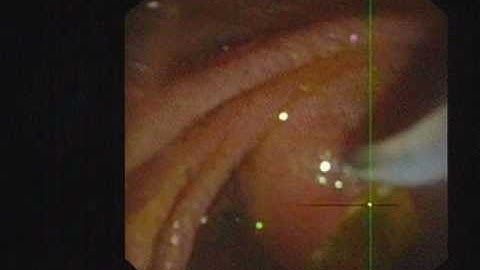

ERCP and stone extraction with precut pappilotomy